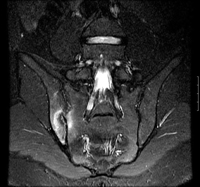

Coronal STIR (short tau inversion recovery) magnetic resonance image showing unilateral (right) sacroiliitis

BMJ 2006;333;581-585. © BMJ Publishing Group Ltd 2009